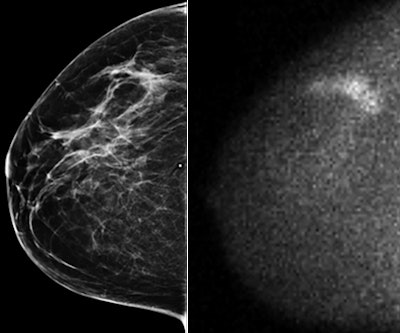

Adding molecular breast imaging (MBI) to conventional mammography finds more cancers in women with dense breast tissue -- and at acceptable radiation doses for screening, according to a new study published in the American Journal of Roentgenology.

The study findings are good news, as mammography's performance diminishes in dense tissue, wrote researchers from the Mayo Clinic in Rochester, MN. To address this problem, additional modalities such as ultrasound and MRI are used, but both have their own drawbacks, including ultrasound's high false-positive rates and MRI's cost. Molecular breast imaging offers another option.

"MBI produces functional images of the breast, which in my opinion is the direction we need to go to overcome the limitations of anatomical imaging in dense breast tissue," lead author Dr. Deborah Rhodes told AuntMinnie.com. "No matter how much you improve your x-ray, at the end of the day it's still an anatomical image."

For this research, Rhodes and colleagues followed up a pilot study they published four years ago (Radiology, January 2011, Vol. 258:1, pp. 106-118). That initial study established that functional imaging did better than anatomical imaging in dense breasts. The current study explored how much MBI's radiation dose can be reduced while still maintaining diagnostic image quality (AJR, February 2015, Vol. 204:2, pp. 241-251).

The researchers included 1,585 asymptomatic women who were characterized with dense breasts based on prior mammography. The women underwent screening mammography with adjunctive MBI at a reduced dose of 8 mCi of technetium-99m (Tc-99m) sestamibi with a cadmium zinc telluride gamma camera. A conventional dose for molecular breast imaging is 20 mCi to 25 mCi. Rhodes' team used either Gamma Medica's LumaGem unit or GE Healthcare's Discovery NM 750b system for the MBI exams.